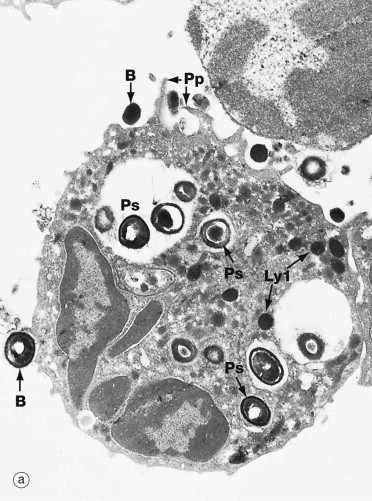

What is this cell?

Neutrophil